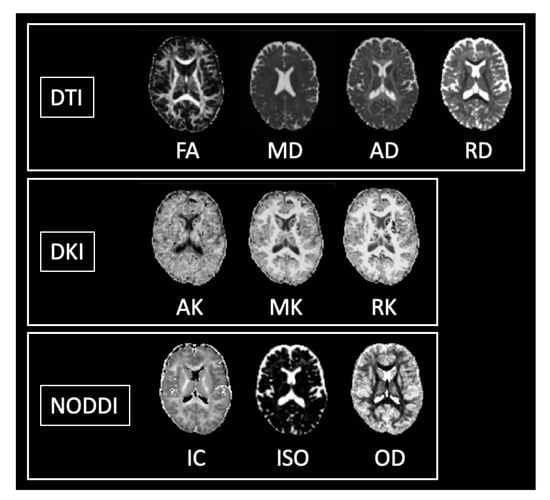

2. Diffusion Tensor Imaging (DTI)

4. Diffusional Kurtosis Imaging (DKI)

5. Neurite Orientation Dispersion and Density Imaging (NODDI)